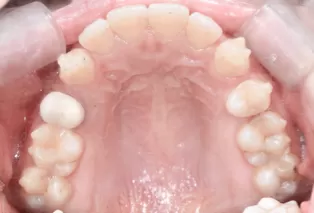

Intraoral photos